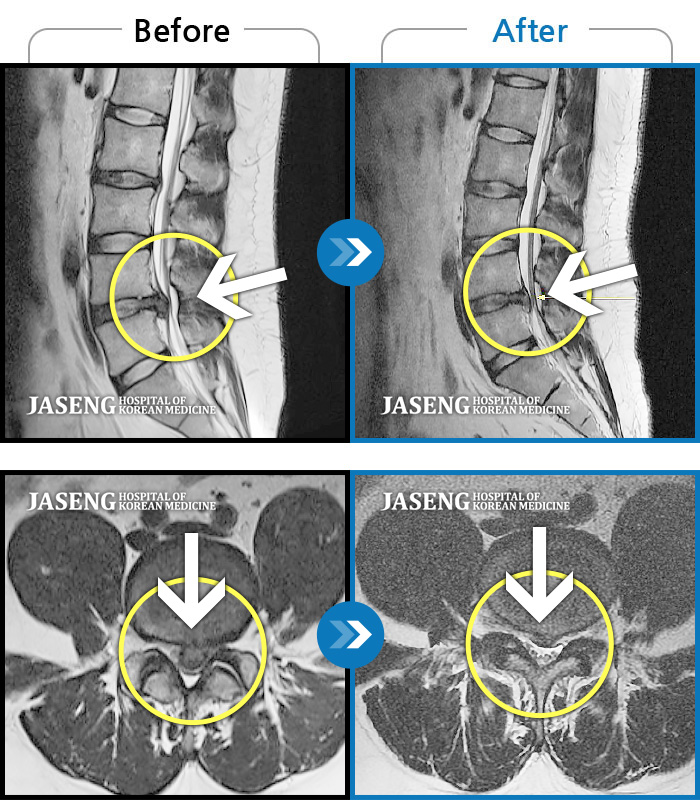

MRI 치료사례

되풀이되는 왼쪽 다리 야간통으로 인한 수면장애와 허리통증